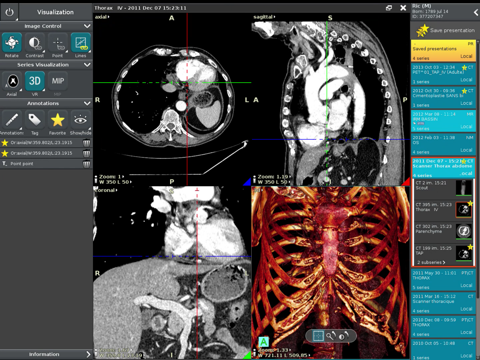

Anywhere Streaming is a DICOM visualization client that connects to Anywhere Server. It provide standard medical image navigation tools surch as : slicing, windowing, MPR, 3D VR, MIP, oblique ... All standard medical image modalities are ...